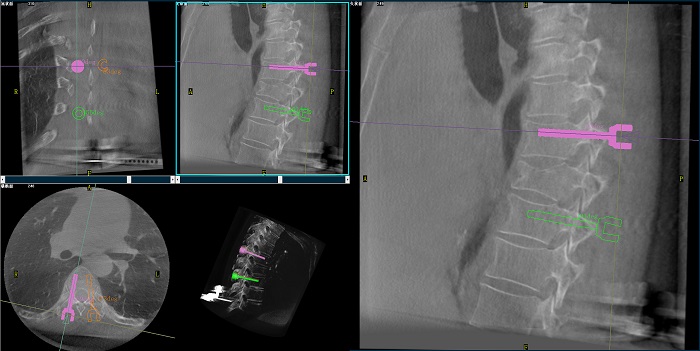

②機(jī)器人輔助胸椎手術(shù)操作難點(diǎn)之路徑規(guī)劃

人體胸椎的椎弓根較腰椎更狹窄,周圍有重要的神經(jīng)和血管,選擇合適尺寸和長度的螺釘至關(guān)重要。螺釘過粗可能損傷椎弓根,過細(xì)容易發(fā)生形變,固定強(qiáng)度不夠;螺釘過長可能穿透椎體前緣,造成損傷,過短則固定不牢。

普愛醫(yī)療手術(shù)導(dǎo)航定位系統(tǒng)解決方案

使用機(jī)器人輔助手術(shù),醫(yī)生不僅可以在影像的引導(dǎo)下,一次性完成多枚螺釘?shù)穆窂揭?guī)劃,提高手術(shù)效率,而且可以精確地選擇螺釘?shù)慕嵌?、直徑和長度,提高手術(shù)的成功率。